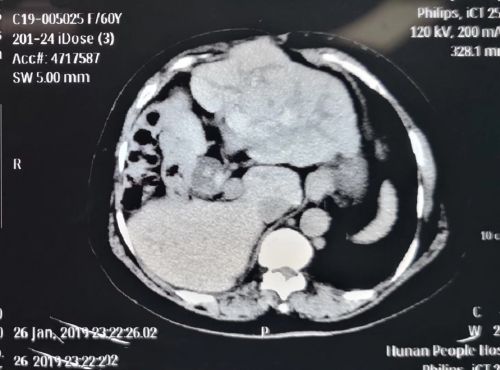

术前影像资料可以看到:肝内充满结石,腹壁缺损。

检查发现,黄女士的肝内外胆管有多发结石,右上腹还有一个直径约16厘米的包块——三次开腹手术后伤口感染形成的巨大腹壁疝。当患者站立时,腹腔内的肠管就会向外凸出,看上去就像身怀六甲。同时,黄女士还有15年的糖尿病史,并且发展为糖尿病肾病,进入尿毒症期,每周要做两三次血液透析。